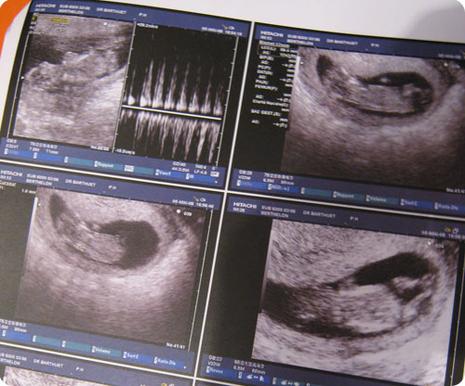

"Expulsion" (comme ils disent dans le milieu médical) prévue le 28 novembre prochain.